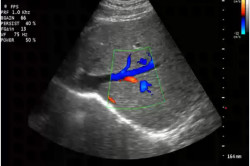

Отражение скорости множества частиц крови (доплеровский сдвиг) кодируется в виде графика и визуального представления изменения движения кровотока. Цветное отображение процесса появляется на черно-белом фоне картинки обычного УЗИ (дуплексное сканирование).

При исследовании производится измерение пиковой систолической скорости увеличения кровотока. Составляется график ее изменения с использованием импульсного допплера. Фиксируется время возрастания скорости кровотока от нулевой до пиковой. Если этот показатель превышает 100 м/с, диагностируется поражение артерий пениса.

Далее анализируется диастолическое изменение кровотока. В фазе ригидности он должен быть равен 0.

Если на этом этапе развития эрекции регистрируется кровоток в венах полового члена, факт свидетельствует о несостоятельности этих кровеносных сосудов.